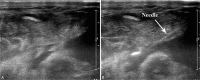

Interventions: When conservative treatment failed, a 2 mL undiluted PA-MSHA preparation was percutaneously injected at the effusion site of the left supraclavicular area under US guidance with aseptic technique. Concomitantly, the drainage tube was clamped for at least 30 minutes. VSports最新版本.

Outcomes: Chyle fistula in both patients were successfully resolved with this technique within 2 or 4 days, without notable side effects V体育平台登录. .

Lessons: US-guided percutaneous injection of PA-MSHA is a simple and effective method to treat chyle fistula following neck dissection, which may serve as a useful addition to the medical treatment for cervical chyle fistula VSports注册入口. .